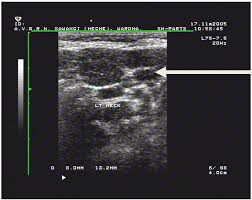

Physical examination/blood and urine tests. Surgical levels of the neck. Ultrasound and mapping of neck lymph nodes. Ultrasound is often one of the first line tests in the detection of cancer. Ultrasound does not show the structures inside joints, dr. Doctors often use ultrasound to guide a needle to do a biopsy (taking out fluid or small pieces of tissue to be looked at under a microscope). It can be used with a fine needle aspiration test or core biopsy test to accurately direct the tip of the needle into the lump. Before the node starts the lesions even very experienced specialist, the device will be able to register an increase, its contour irregularity, violation of the structure. The ultrasound technician (sonographer) may position your head to better access the side of your neck. Likewise, how do they test for thyroid cancer? A biopsy can be performed in cases where ultrasound cannot differentiate benign from malignant tumours. Keep in mind, however, that an ultrasound alone cannot make the diagnosis of cancer. Fna might also be used in patients whose cancer has been treated by surgery and/or radiation therapy, to help find out if a neck mass in the treated area is scar tissue or if it's a return (recurrence) of the cancer.

Ultrasoundis very sensitive and showsmany nodules that cannot be felt. In addition, the following tests may be used to diagnose head and neck cancer: Ultrasound does not show the structures inside joints, dr. Fna might also be used in patients whose cancer has been treated by surgery and/or radiation therapy, to help find out if a neck mass in the treated area is scar tissue or if it's a return (recurrence) of the cancer. Ultrasound technology cannot find ulcers, but other types of diagnostic tests can. Some research explores the potential for finding ulcers with an ultrasound, but experts do not have enough data to recommend it. The path report states loose fragments of poorly differentiated malignant epithelial cells with enlarged hyperchromatic irregular nuclei and apoptosis are seen in a hemorragic background that includes few scattered atypical keratinized squamous cells. Testing lymph nodes the lymph nodes in the neck are often the first place cancer cells spread to outside the primary site. Ultrasoundimaging is a noninvasive medical test that helps physicians diagnose and treat medical conditions. If this lump is of concern then a biopsy would be the next step. Cancer of the liver or fatty. Optimal positioning and exposure of the neck for ultrasound of the thyroid and parathyroid glands (a, b) and lateral neck for lymph node examination and mapping (c).while the vast majority of patients are supine on the exam table with a pillow supporting the shoulders to allow gentle neck extension, keep in mind that some patients have beautiful anatomy (d) that allows ultrasound exam even in. Abnormal enlargement of the spleen.

The ultrasound technician (sonographer) may position your head to better access the side of your neck. Each case is different and your doctor will explain your treatment options. Ultrasound cannot tell whether a tumor is cancer. The sonographer then gently presses the transducer against the side of your neck. Ultrasound and mapping of neck lymph nodes.

Cureus Evaluation Of B Mode And Color Doppler Ultrasound In The Diagnosis Of Malignant Cervical Lymphadenopathy from assets.cureus.com If cancer is found in a lymph node, you may need a neck dissection or other additional treatment. A neck ultrasound may help diagnose (find): Throat cancer is often easily seen by an ent exam. The sonographer then gently presses the transducer against the side of your neck. The gel helps transmit the ultrasound waves back and forth. Level i constitutes lymph nodes above the anterior and posterior bellies of the digastric muscle cephalad to the hyoid bone and inferior to the inferior border of the mandible and includes the submental group of nodes. If the person has a lump in the neck, an fna can show if the mass is from cancer spread. Cysts or abnormal growths in the liver, spleen, or pancreas.

Confirming that a lump in the neck is developing from the thyroid or connected tissue. The sonographer then gently presses the transducer against the side of your neck. Identification of a suspicious lymph node increases the likelihood of cancer and may warrant fna of the node in lieu of the thyroid (see fig. Surgical levels of the neck. This test will usually help determine that the nodule has a low chance of being cancerous (has characteristics of a benign nodule), or that it has some characteristics of a cancerous nodule, and therefore a biopsy is indicated. The ultrasound technician (sonographer) may position your head to better access the side of your neck. During a physical examination, the doctor feels for any lumps on the neck, lips, gums, and cheeks. Abnormal enlargement of the spleen. In my experience an ultrasound won't tell you if you have cancer, it just shows a lump. If cancer is found in a lymph node, you may need a neck dissection or other additional treatment. Doctors often use ultrasound to guide a needle to do a biopsy (taking out fluid or small pieces of tissue to be looked at under a microscope). Throat cancer is often easily seen by an ent exam. It can detect abnormal tissues, growths, and cysts and give a suspicion of cancer based on how those images look.